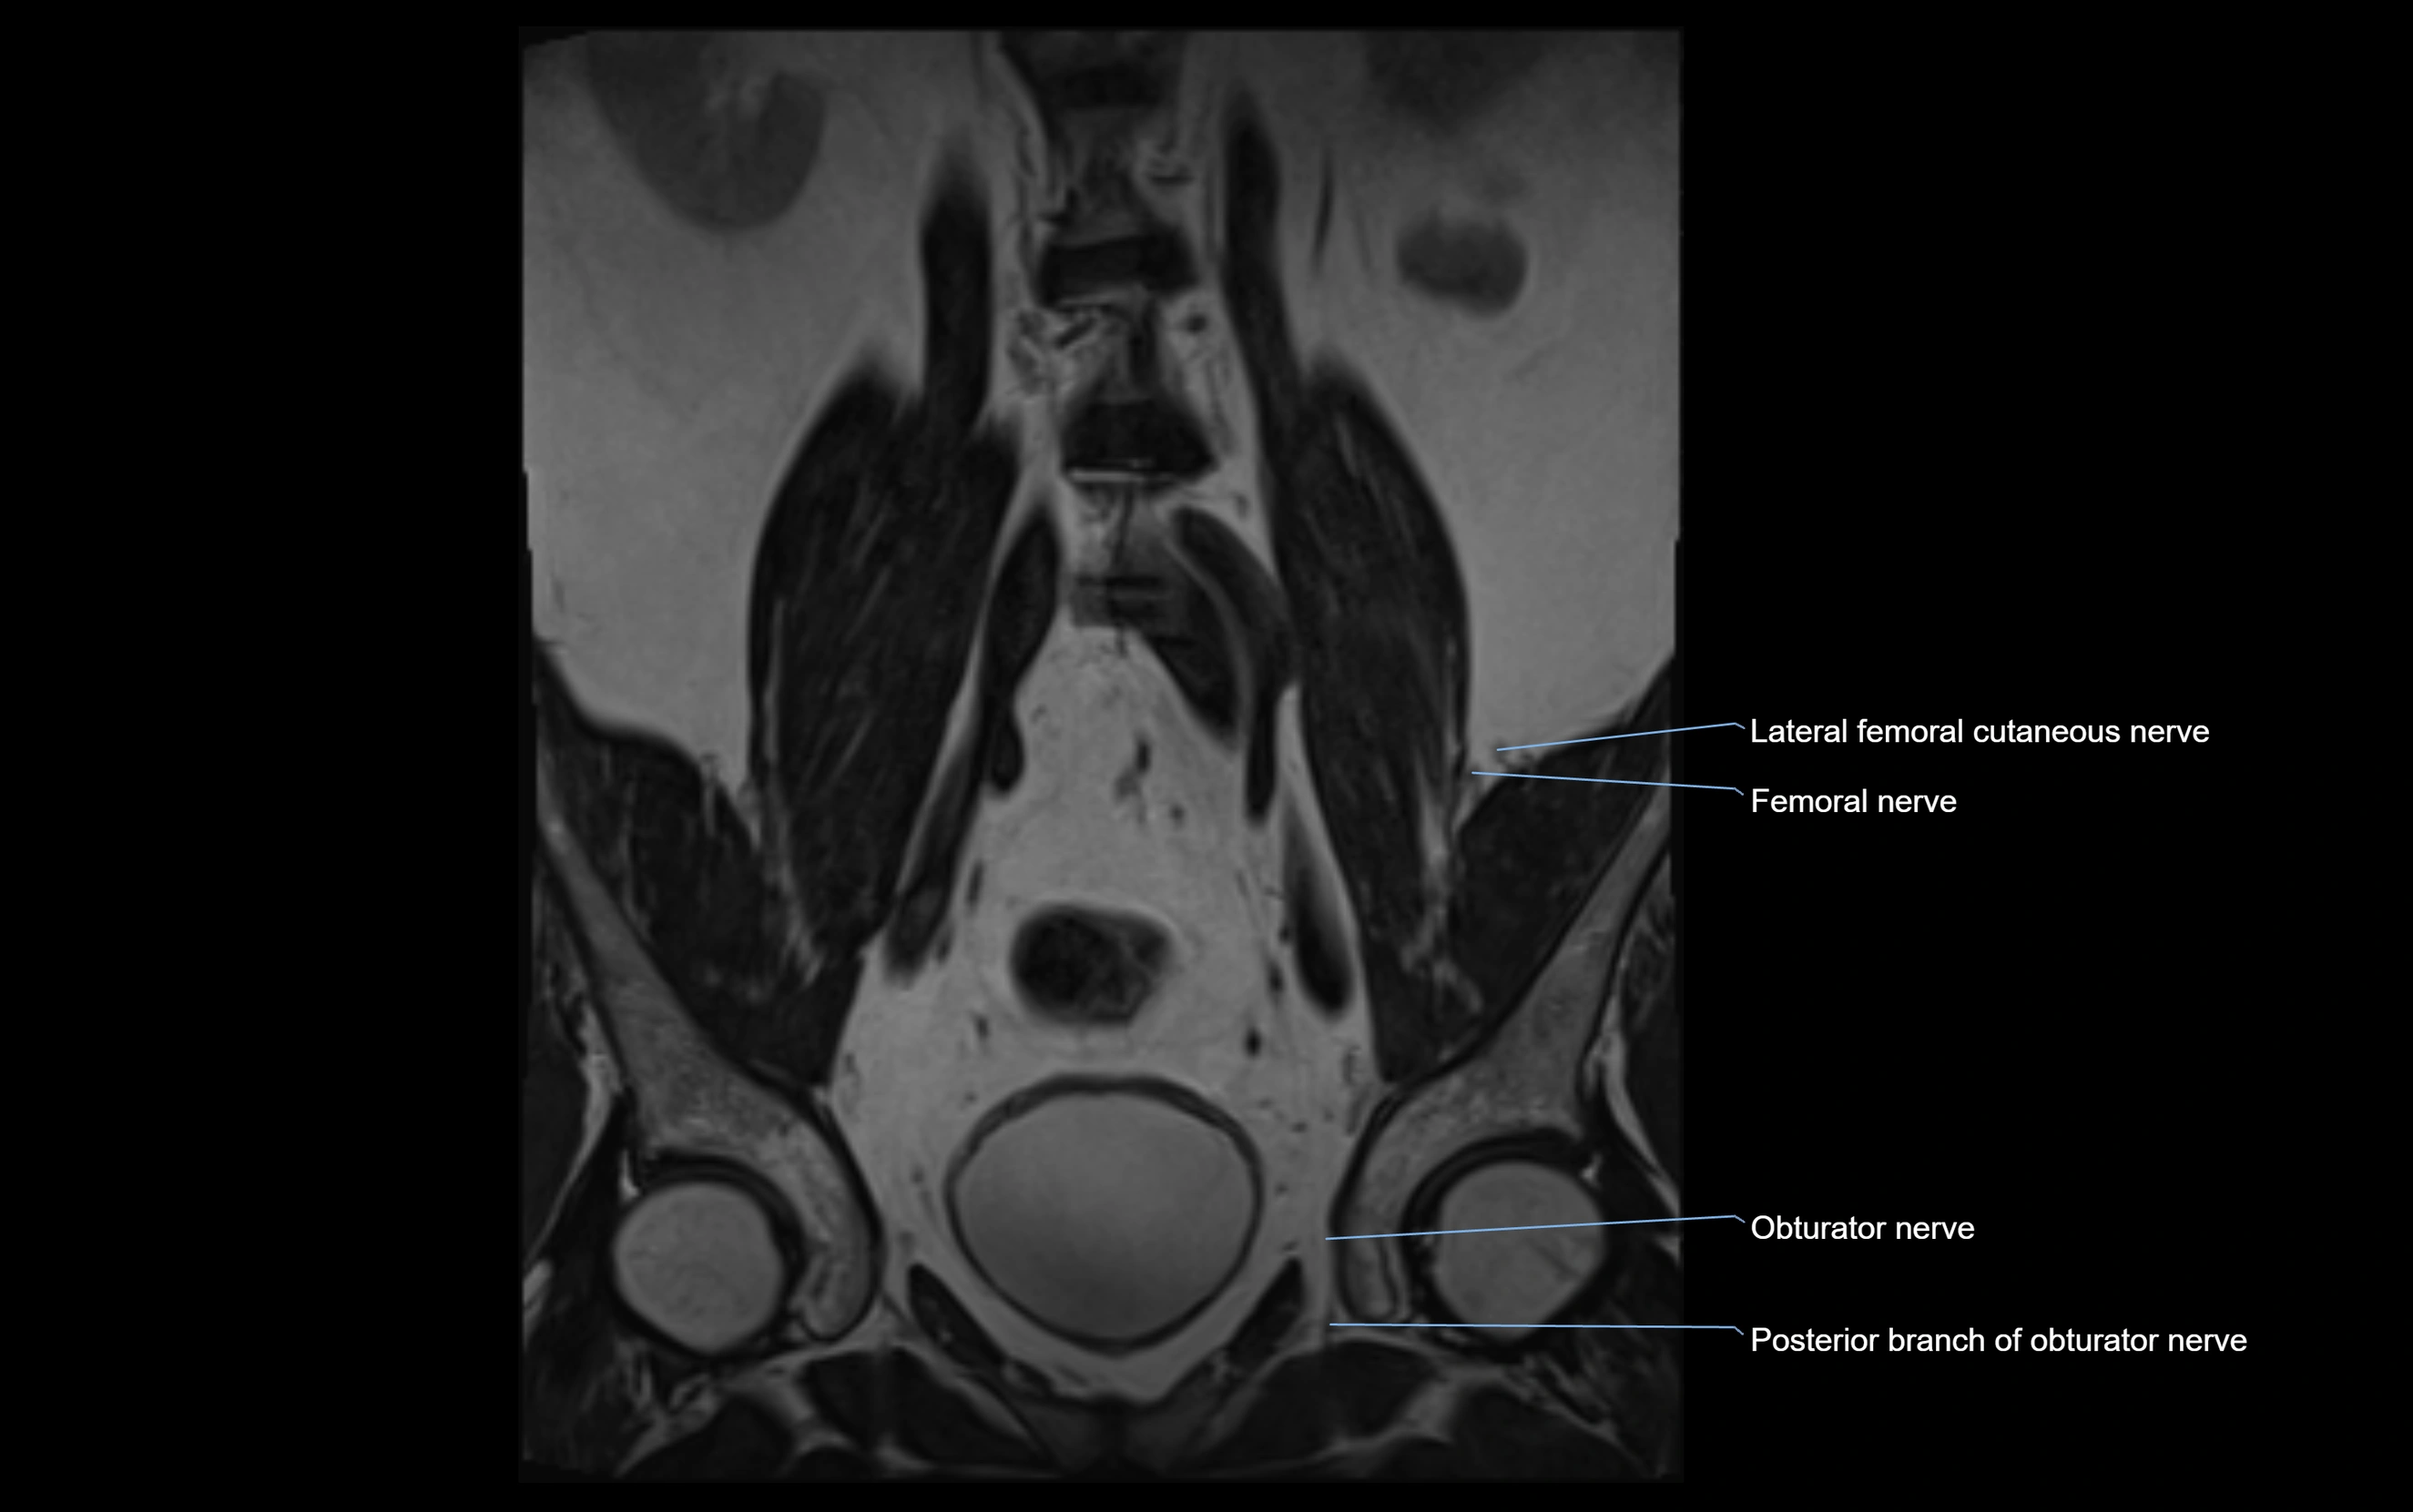

MRI Appearance

T1-weighted images:

• Nerve appears as a very thin low-to-intermediate signal intensity structure

• Surrounded by bright fat, aiding visualization

T2-weighted images:

• Nerve shows intermediate to mildly hyperintense signal compared to muscle

• Pathological involvement appears brighter

STIR (Short Tau Inversion Recovery):

• Normal nerve appears dark

• Inflamed or entrapped nerve appears bright hyperintense

T1 Fat-Sat Post-Contrast:

• Normal nerve enhances minimally

• Pathologic nerve (neuritis, entrapment, tumor infiltration) shows focal or diffuse enhancement

3D T2 SPACE / CISS:

• Nerve appears intermediate to mildly hyperintense compared to muscle

• Surrounded by bright fat or CSF, improving visualization

• Best sequence for mapping small pelvic nerves such as the anococcygeal